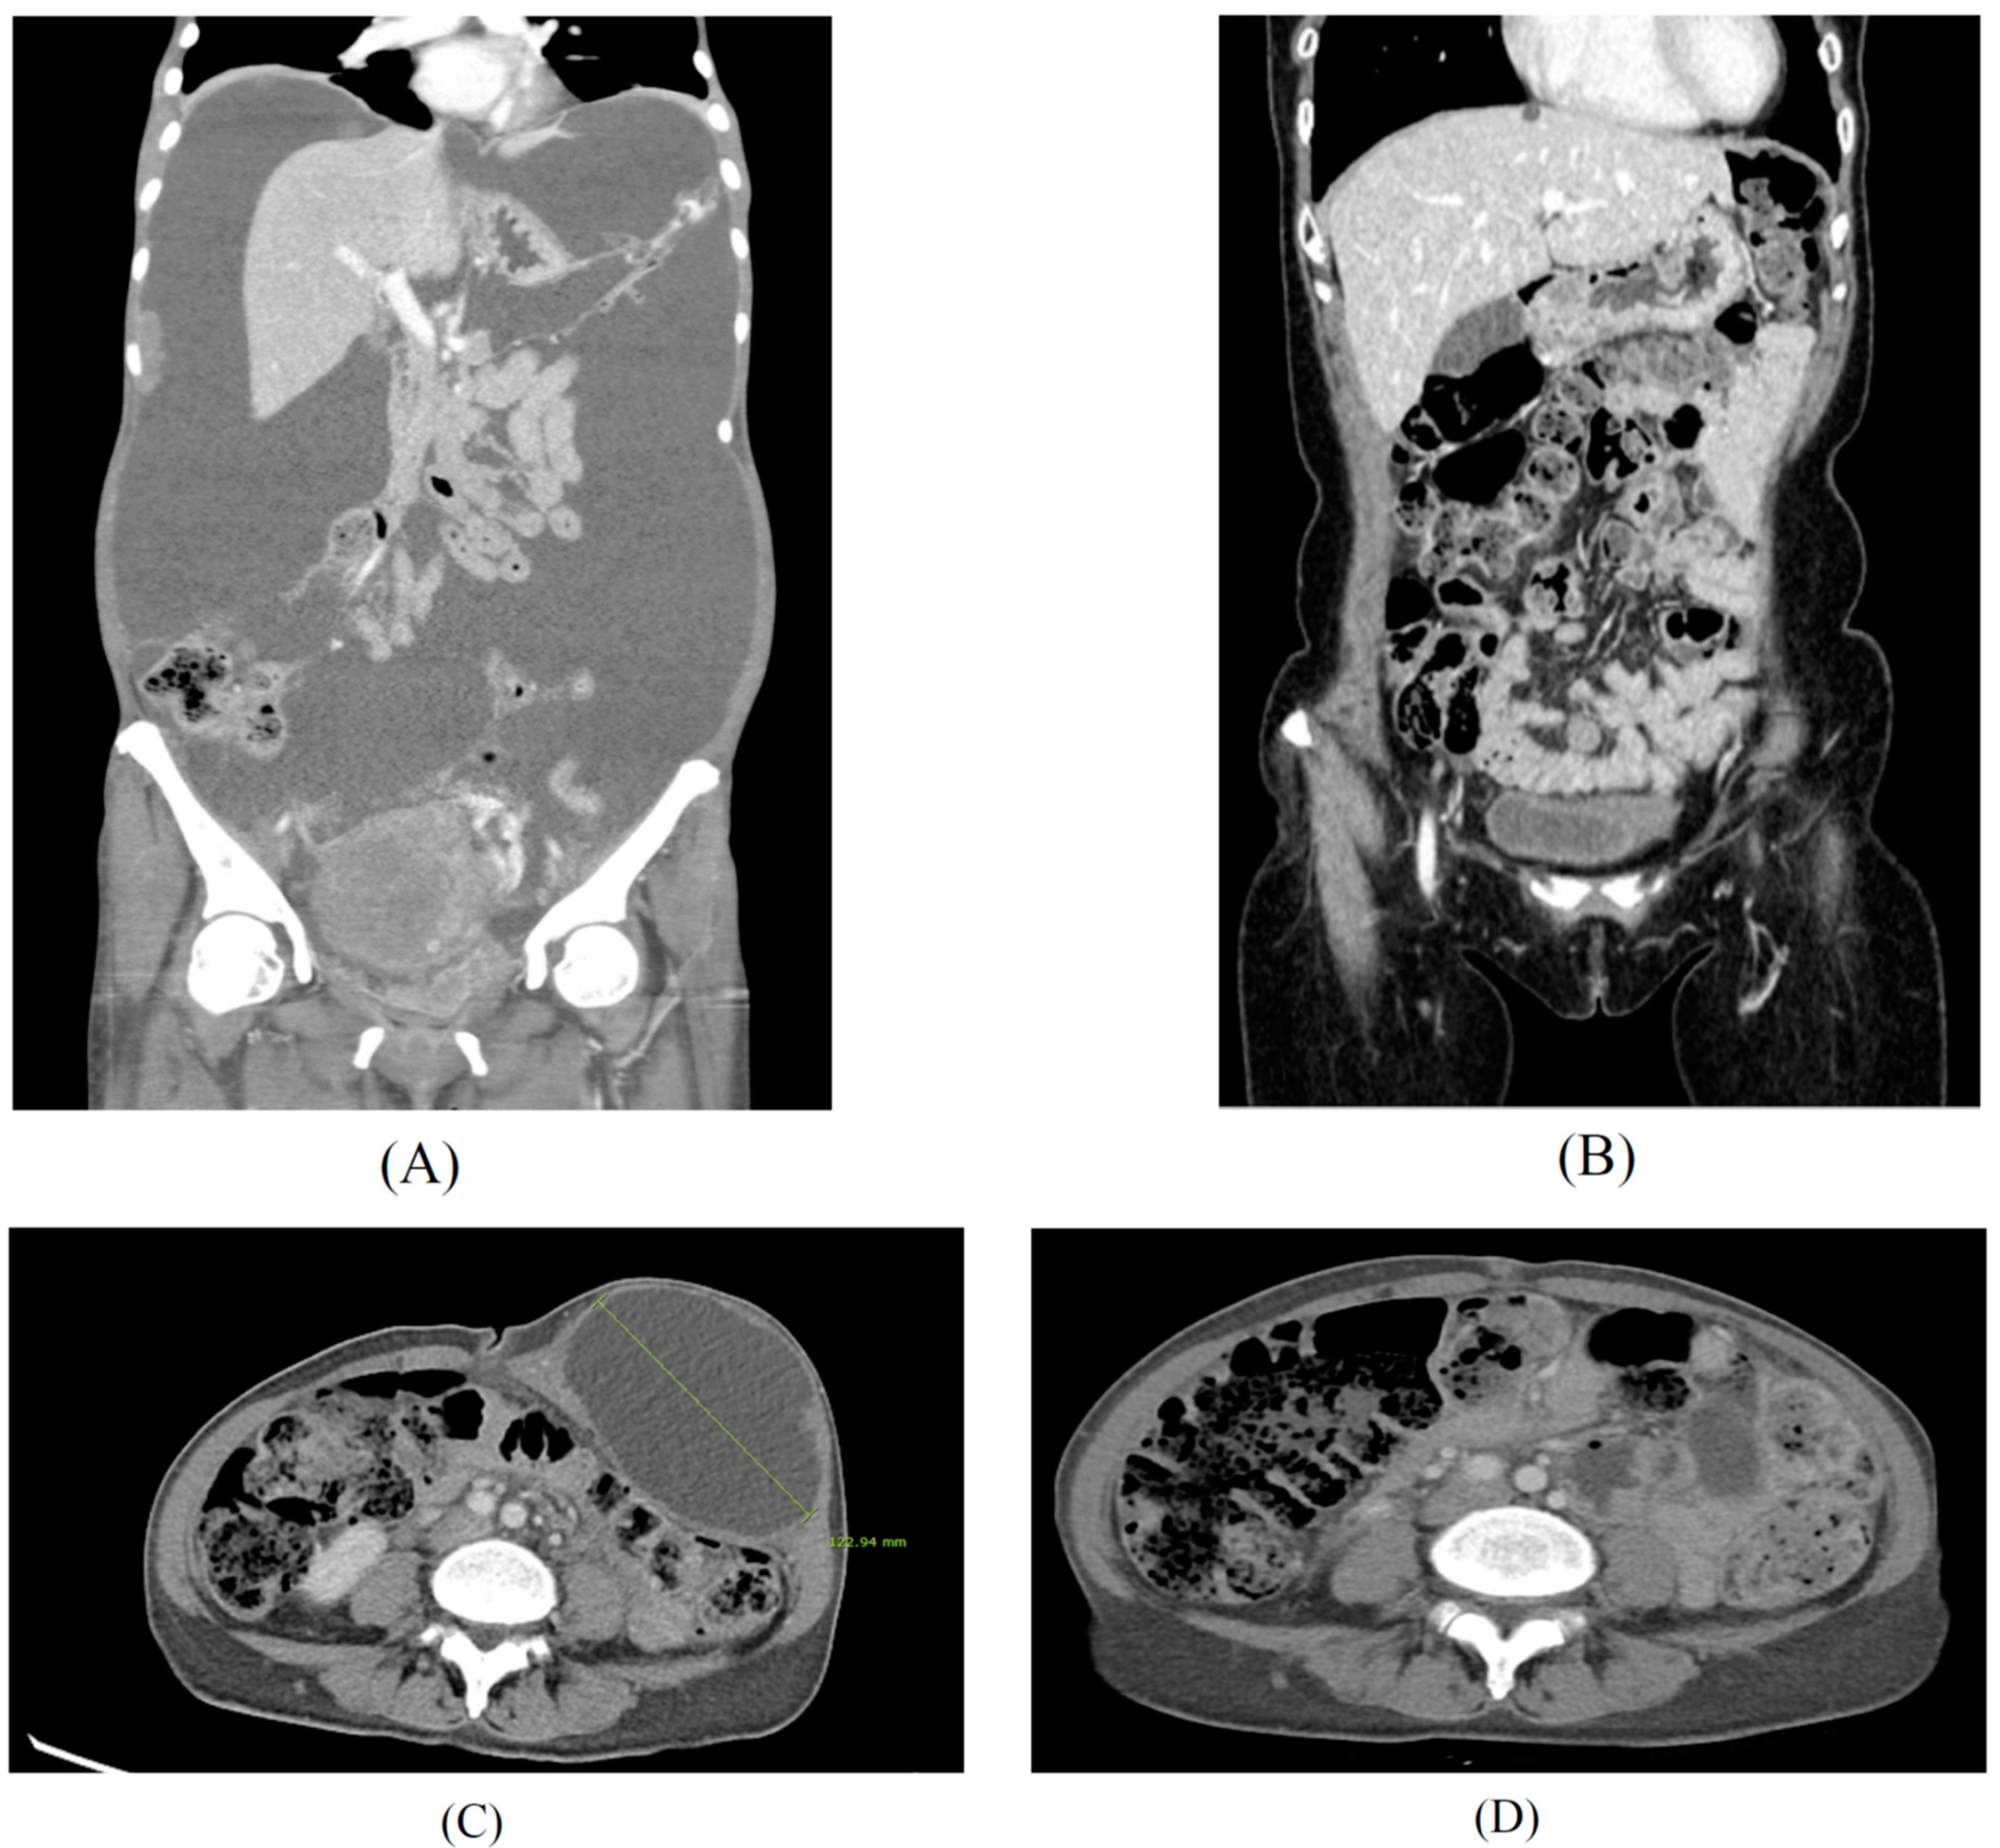

Figure 4.

High doses of sodium selenite in treatment of advanced metastasis cancer patients. Case 1: Findings of abdomino-pelvic CT before (A) and after (B) the multidisciplinary treatment for a 51-year-old patient diagnosed with advanced stage ovarian cancer. Case 2: Findings of abdomino-pelvic CT before (C) and after (D) the integrative treatment for a 48-year-old patient diagnosed with recurrent ovarian cancer after primary intensive pelvic surgery with adjuvant chemotherapy, since 2017. Peritoneal carcinomatosis with massive ascites (A) and no evidence of disease (B) after 18 months of chemotherapy, interval debulking surgery, and PARP inhibitor maintenance therapy with high dose sodium selenite treatment according to regimen of Table 1 (SIMCH). Metastatic para-aortic lymph nodes with 12 cm-sized port site metastatic mass at left lower abdominal wall was noted (C), and no evidence of disease at left lower abdomen and stable disease of metastatic lymph nodes (D) after 16 months of metastatectomy of abdominal wall and maintenance immune checkpoint inhibitor (pembrolizumab) with high dose sodium selenite treatment according to regimen of Table 1 (SIMCH).